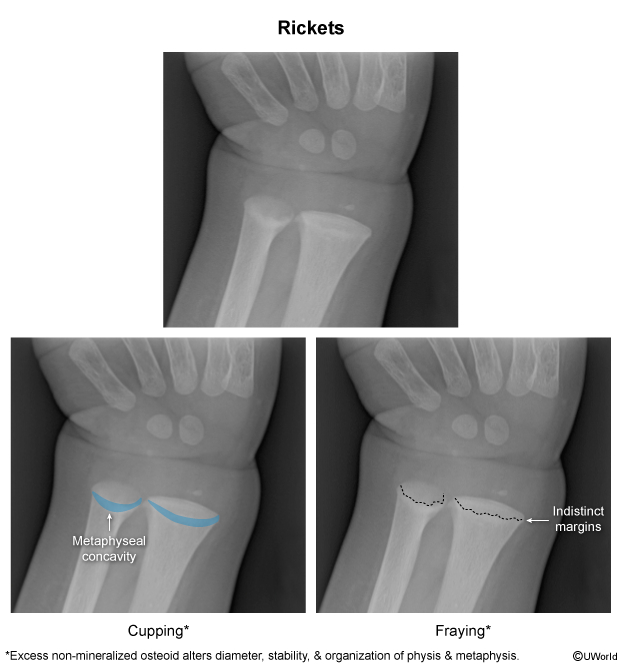

- Rickets is usually diagnosed through radiographic (X-ray) examination of the long bones.

- Findings may include:

- Osteopenic bone shafts (low bone density).

- Widened growth plates.

- Frayed and cupped metaphyseal ends (irregular and blurred bone ends).